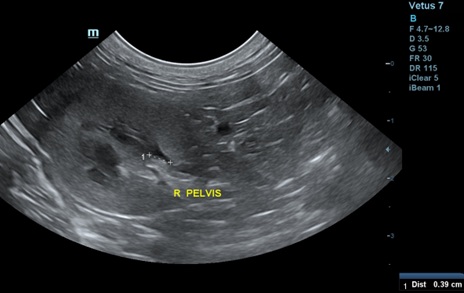

신우는 보통 보이지 않으나, trans view를 잘 잡으면 보일 수 있습니다(그림 2). 신우의 폭은 1-2mm로 무에코의 선으로 관찰됩니다. 수액 투여 시에는 일시적 확장이 있으며, 결석으로 인한 요도폐색, 종양, 이소성 요관이나 신우신염이 있을 때는 확장이 될 수 있습니다(Table 2, 그림 3). 또한 leptospirosis, 신장의 말기 상태나 신장이식 등에서도 나타날 수 있습니다3).